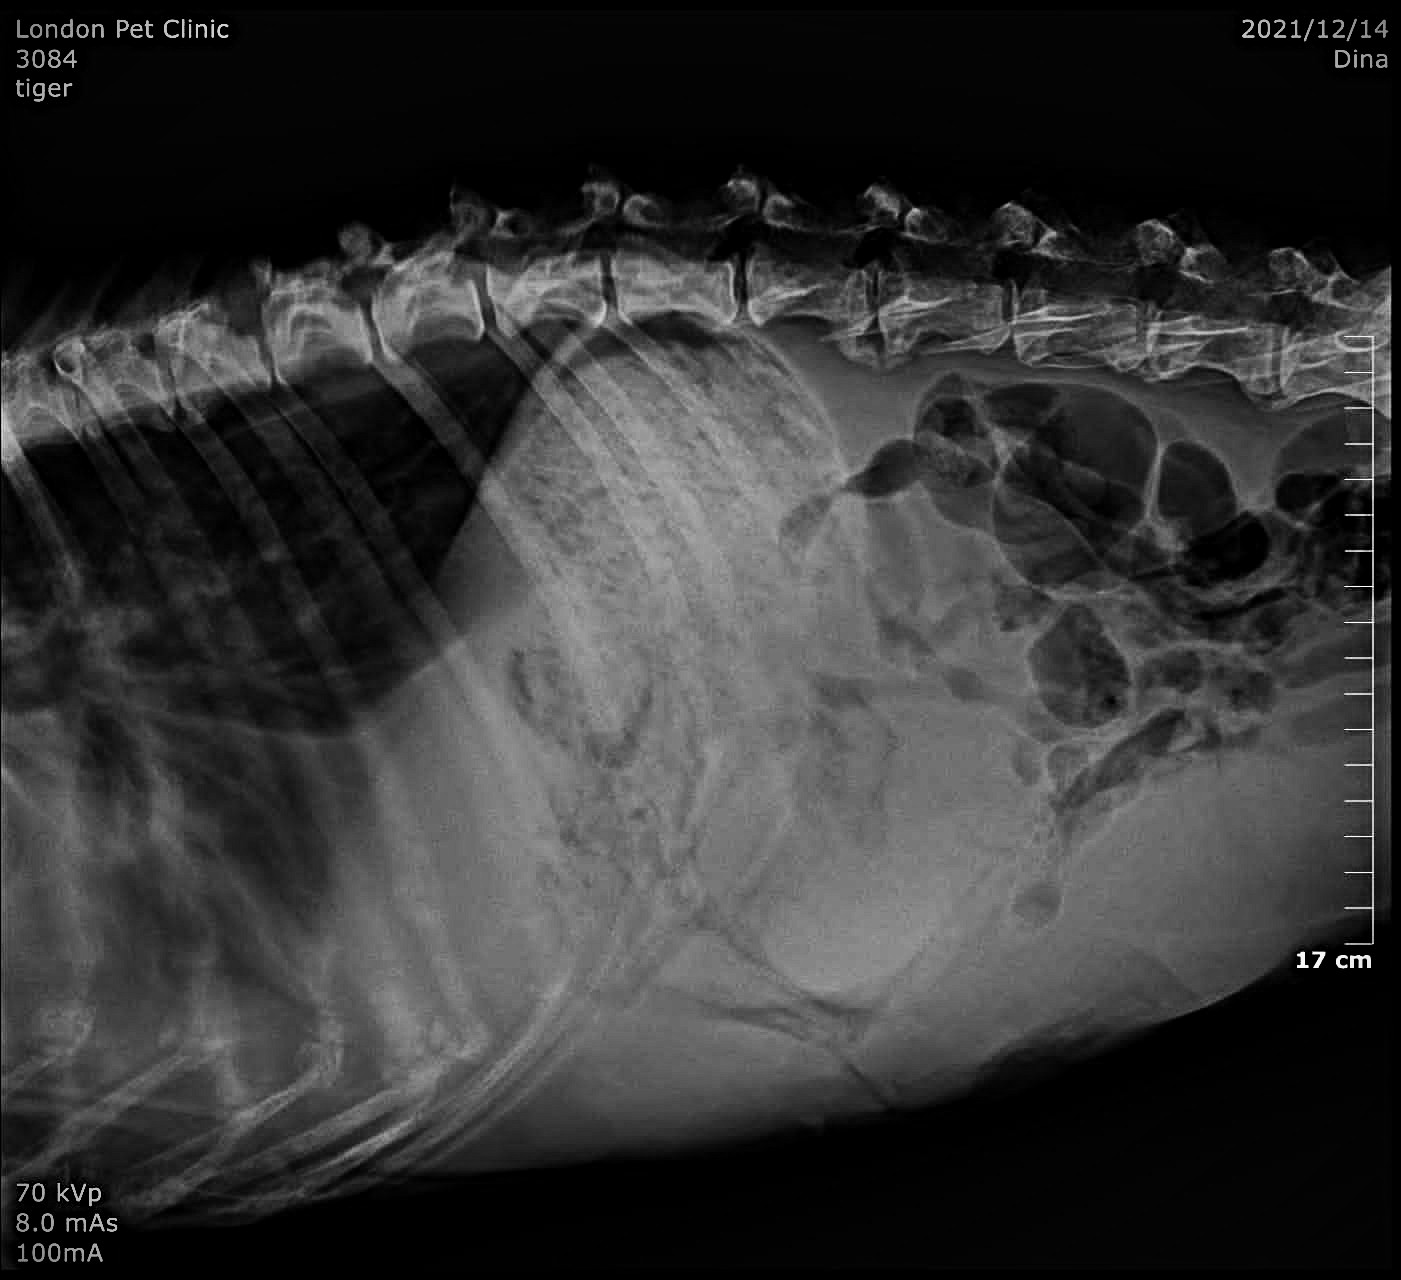

Abdominal Ultrasound:

• Large, irregular splenic masses (~18 cm )

• Free abdominal fluid

• No obvious liver metastases, but small hypoechoic nodules present

• Thoracic Radiographs:

• No obvious pulmonary metastases